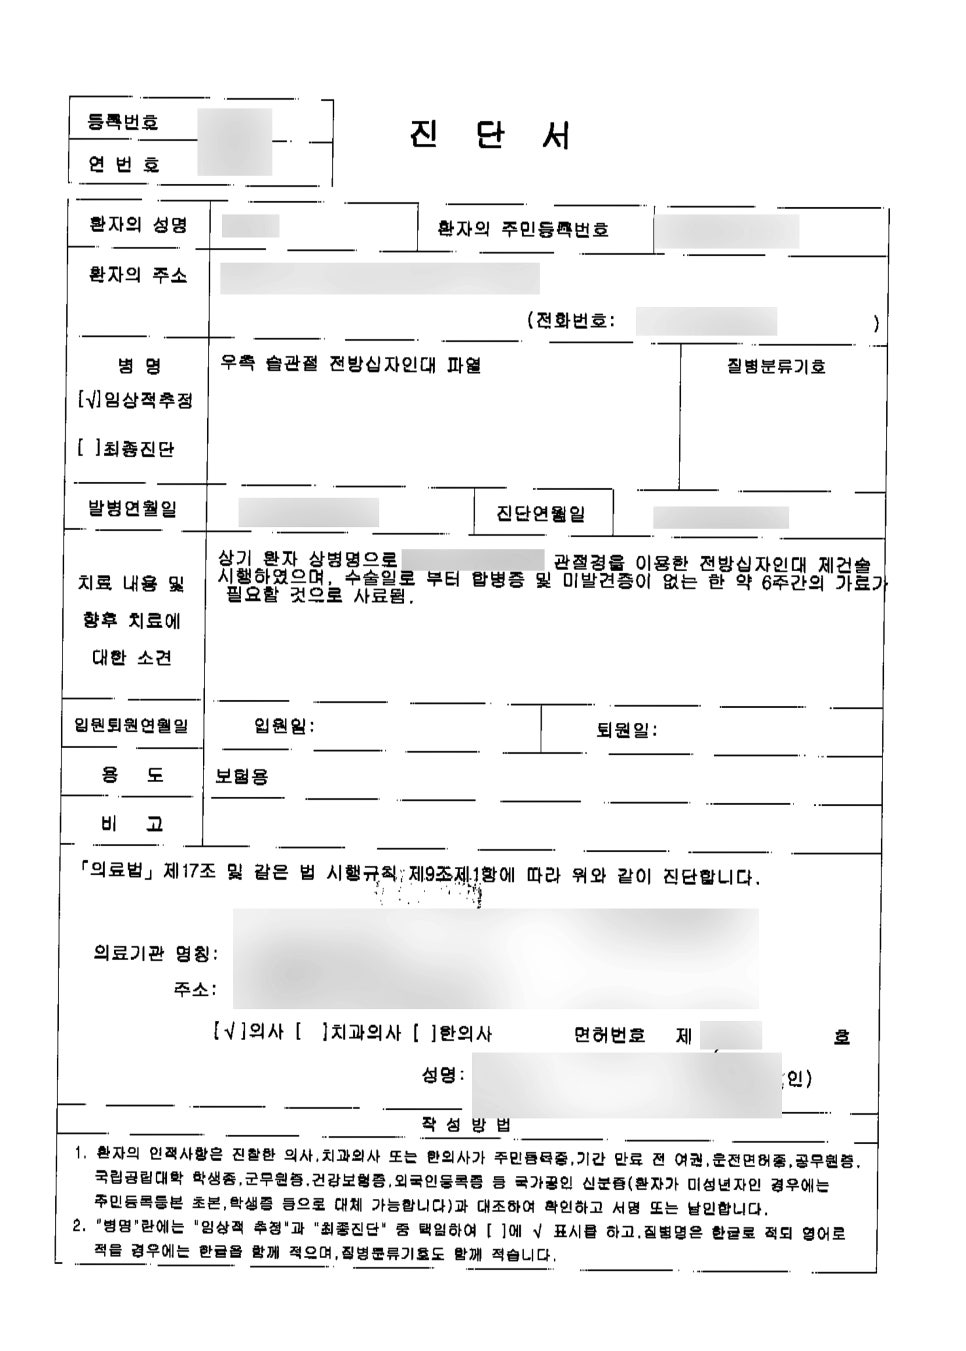

어떻게 믿을 수 있어? 라고 생각하셔도~ 오늘 보시는 진단서나 후유장해진단서를 함께 보시고 나면 생각이 바뀌실 겁니다 ^_^

친구들과 가진 좋은 시간에.. 십자인대파열로 후유장해까지 겪게 되셨으니 정말 마음이 안좋으실거예요 ㅠㅠ 진단명은, 진단서에서 나와있는 것처럼

[우측 슬관절 전방십자인대파열]

관절경을 이용하여 전방십자인대 제건술을 시행하였으며, 수술일로 부터 미발견증 및 합병증 이 없는한 6주간의 가료가 필요한 것으로 사료 되었다고 나와있는 것을 확인할 수 있습니다. 진단서에 나와있는 진단명을 문의시 정확하게 알려주시면 빠른 상담에 많은 도움이 됩니다^^